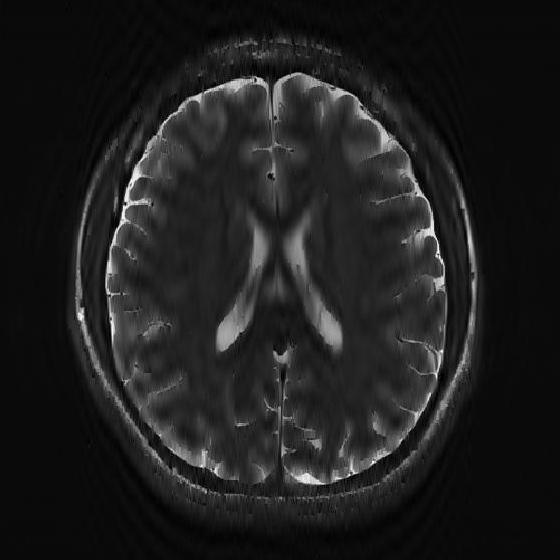

VII-D Application of the 2D-R-FFAST for MR imaging

Refer to caption

(a) Log intensity plot of the 2D-DFT of the original ‘Brain’ image. The red enclosed region is fully sampled and used for the stable inversion.

(b) Original ‘Brain’ image in spatial domain.

(c) Reconstructed ‘Brain’ image using the 2D-R-FFAST architecture along with the fully sampled center frequencies. The total number of Fourier measurements used is 60.18%percent60.1860.18\%.

(d) Log intensity plot of 2D-DFT of the original ‘Brain’ image, after application of the vertical difference operation.

(e) Differential ‘Brain’ image obtained using the vertical difference operation on the original ‘Brain’ image.

(f) Differential ‘Brain’ image reconstructed using the 2D-FFAST algorithm from 56.71%percent56.7156.71\% of Fourier measurements.

Figure 11: Application of the 2D-FFAST algorithm to reconstruct the ‘Brain’ image acquired on an MR scanner with dimension 504×504504504504\times 504. We first reconstruct the differential ‘Brain’ image shown in Fig. 11(e), using d=3𝑑3d=3 stage 2D-R-FFAST architecture with 151515 random delays in each of the 333 stages of the 2D-FFAST architecture. Additionally we acquire all the Fourier measurements from the center frequency as shown, by the red enclosure, in Fig. 11(a). Then, we do a stable inversion using the reconstructed differential ‘Brain’ image of Fig. 11(f) and the fully sampled center frequencies of Fig. 11(a), to get a reconstructed full ‘Brain’ image as shown in Fig. 11(c). Our proposed two-step acquisition and reconstruction procedure takes overall 60.18%percent60.1860.18\% of Fourier measurements.

In this section, we apply the 2D-R-FFAST algorithm to reconstruct a brain image acquired on an MR scanner with dimension 504×504504504504\times 504. In MR imaging the measurements are acquired in the Fourier domain and the task is to reconstruct the spatial image from significantly less number of Fourier measurements [17]. To reconstruct the full brain image using 2D-R-FFAST, we perform the following two-step procedure:

• Differential space signal acquisition: We perform a vertical finite difference operation on the image by multiplying the 2D-DFT signal with 1e2πıωx1superscript𝑒2𝜋italic-ısubscript𝜔𝑥1-e^{2\pi\imath\omega_{x}}. This operation effectively creates an approximately sparse differential image, as shown in Fig. 11(e), in spatial domain and can be reconstructed using 2D-FFAST. Note, that the finite difference operation can be performed on the sub-sampled data and at no point we access all the input Fourier measurements. The differential brain image is then sub-sampled and reconstructed using a 333 stage 2D-FFAST architecture. Also, since the brain image is approximately sparse, we take 151515 delay sub-streams in each of the 333 stages of the 2D-FFAST architecture, instead of 333 delay sub-streams as in the exactly sparse case. The 2D-R-FFAST algorithm reconstructs the differential brain image using 56.71%percent56.7156.71\% of Fourier measurements.

• Inversion using fully sampled center frequencies: After reconstructing the differential brain image, as shown in Fig. 11(f), we invert the finite difference operation by dividing the 2D-DFT measurements with 1e2πıωx1superscript𝑒2𝜋italic-ısubscript𝜔𝑥1-e^{2\pi\imath\omega_{x}}. Since the inversion is not stable near the center of the Fourier domain, only the non-center frequencies are inverted. The center region of the 2D-DFT is fully sampled and used in the inversion process.

• Overall we use a total of 60.18%percent60.1860.18\% of Fourier measurements to reconstruct the brain image using the 2D-R-FFAST algorithm along with the fully sampled center frequencies. The resulting signal-to-noise ratio of the reconstructed image is 4.51734.51734.5173 dB. While the reconstruction error is not as good as state-of-the-art compressed sensing MRI results, we note that the 2D-R-FFAST has both low computational complexity and low sample complexity , which none of the state-of-the-art compressed sensing results in MRI can achieve.